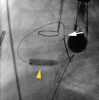

Methods/results: A full-term infant girl (2.9 kg) referred for hypoxia (80% with room air) and murmur was found to have DORV, interrupted inferior vena cava, and restrictive VSD (95-mmHg gradient). Transhepatic access was performed, and an internal mammary (IM) catheter was advanced through the atrial septal defect and into the left ventricle. By transesophageal echocardiographic guidance, a Baylis radiofrequency perforation wire was used to cross the ventricular septum, and the defect was enlarged using a 4-mm cutting balloon. A bare metal stent then was deployed to maintain the newly created VSD. The patient did well after the procedure but required pulmonary artery banding 4 days later. She returned 5 months later with cyanosis and the development of obstructing right ventricle muscle bundles, requiring further surgical palliation.